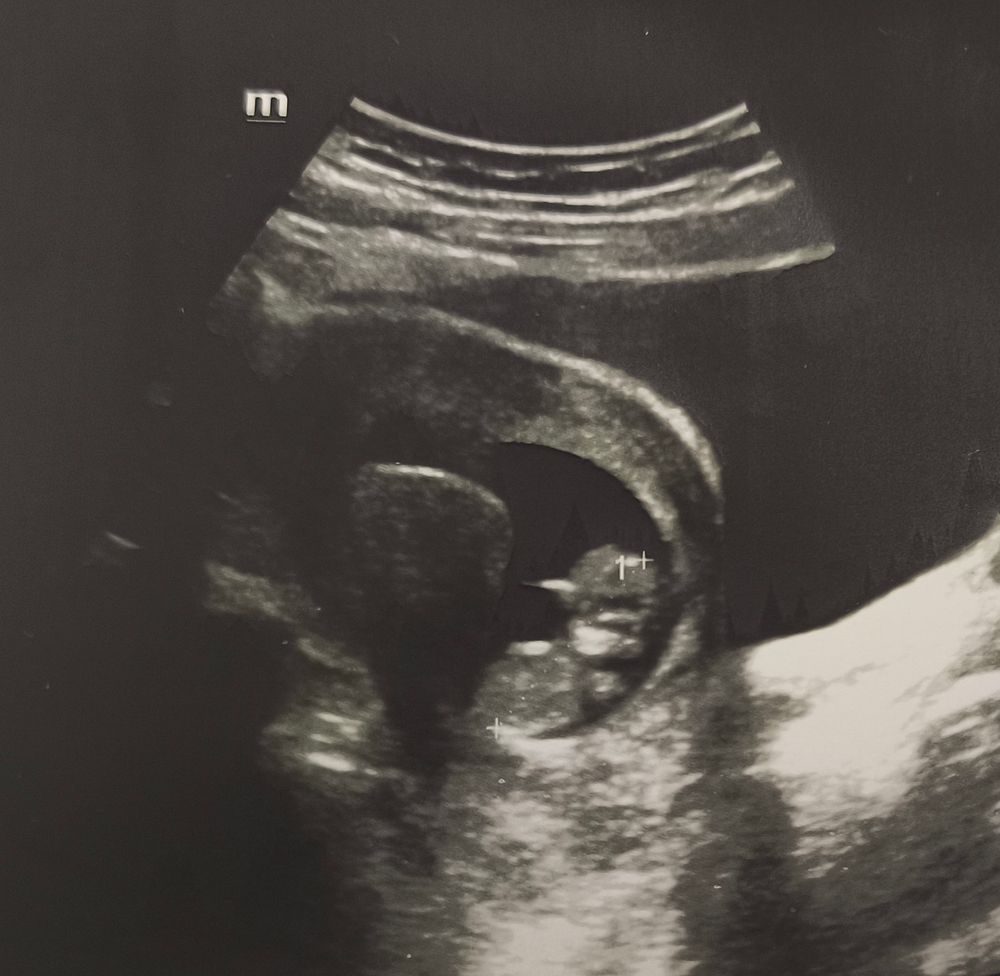

Сегодня была на УЗИ, сказали что тонус, нужно свечи папаверин, болей нет, ничего не беспокоит. Может кто-то разбирается в УЗИ? Кружок слева это точно тонус?

Да у меня такой же бугорок 😅 вообще еще из за эндометриоза…он как креветка только назад изгибался. Даже жалко стало его